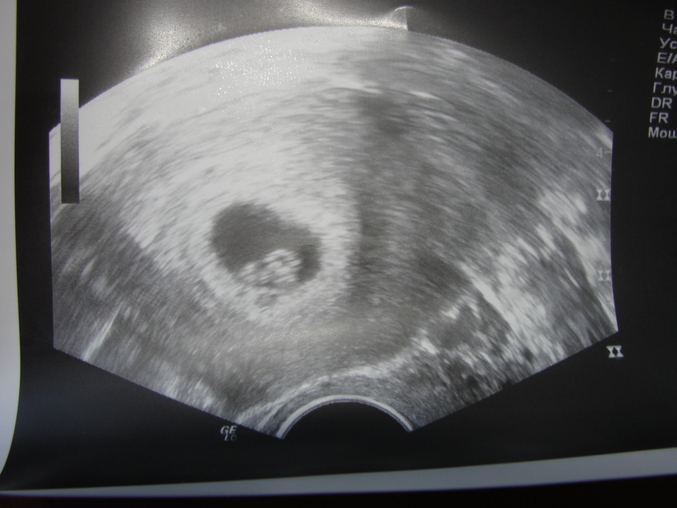

Протоколы ЭКО (Все о них, все об этом периоде+Гиперстимуляция)девочки все хорошо мы дома!наше первое фото!!!! и вот мы какие красивые нам 4недели и оден день=)))